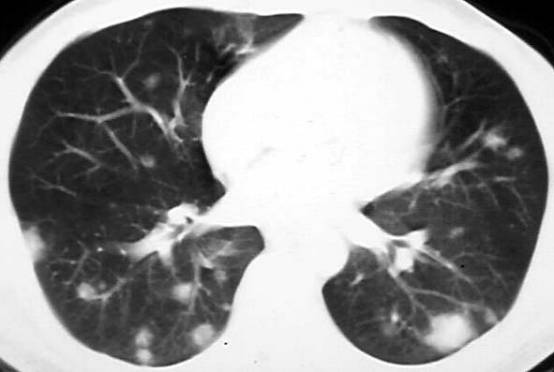

蕈样肉芽肿1例肺部CT影像表现

案例:活动后呼吸困难,干咳一月余。 医学百科网 | YxBaike.Com

分析:蕈样肉芽肿是T细胞淋巴瘤的一种,早期主要发生在皮肤,表现为湿疹或牛皮癣样改变。随着病情进展,各个器官均有不同程度累及,最常见为淋巴结、肝和肺,约50%的患者有肺部受累。影像学表现多种多样,双肺多发的实性结节,片状致密影,或弥漫性网状结节样改变,可伴有胸腔积液,部分病程发展较快,与大叶性肺炎相似。